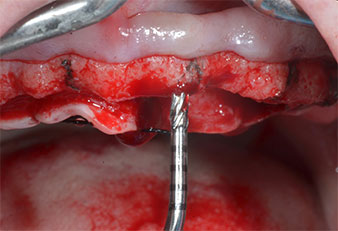

Para marcar las posiciones del implante y realizar la preparación piloto, se utilizó un inserto piezoeléctrico (Piezomed I1) con revestimiento de diamante y forma de llama (figura 3). Se tomaron precauciones para realizar movimientos hacia arriba y hacia abajo, con una potencia reducida, una irrigación completa y una baja presión (por debajo de 300 g). A continuación, se aplicó un inserto piloto (Piezomed I2A/I2P) para aumentar el diámetro inicial de 2 mm de los sitios de implante (figura 4), seguido de un inserto de 3 mm (Fig. 5).